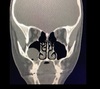

35

Dx

Hipertrofia de cornetes

36